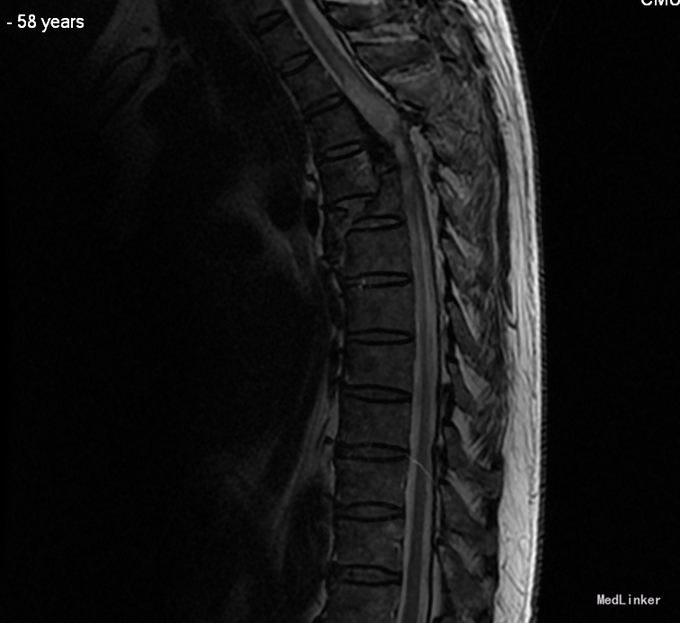

患者于2014-08-13日11:30左右骑摩托车摔倒,伤后一过性意识不清,清醒后感觉胸部疼痛,双下肢活动受限,急诊送至盘锦市宽甸县中心医院,行胸CT、头CT、胸椎三维CT,提示为胸椎骨折,急诊行面部伤口清创缝合,具体治疗不详。患者及家属为求系统治疗,急来我院,急诊予以行辅助检查,提示:胸椎骨折;急诊以“多发外伤”为主诊断收入我科.

平乳头以下感觉减退,平耻骨联合以下感觉运动消失。上臂肌力(R5,L5),前臂肌力(R5,L5),手掌掌屈肌力(R5,L5),手掌背伸肌力(R5,L5)。双手握力(R5,L5)。髂腰肌肌力(L0级,R0级),伸膝力(L0级,R0级),足背伸力(L0级,R0级),足跖屈肌力(L0级,R0级),

诊断:胸3-6椎体骨折,胸髓损伤,双下肢全瘫。 入院后完善检查,查无手术禁忌症后行胸椎骨折后路切开复位椎板减压椎弓根钉内固定术